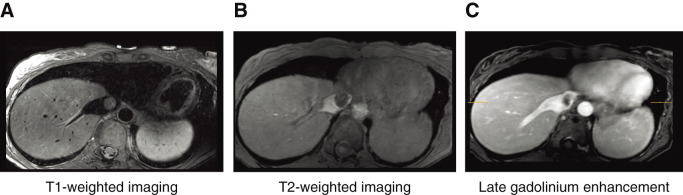

We experienced a case in which a myxoma in the inferior vena cava (IVC) was surgically removed along with the IVC using deep hypothermic circulatory arrest. A 42-year-old female with no subjective symptoms was incidentally found to have a mass in the IVC at the junction of the hepatic veins on contrast-enhanced computed tomography. Ultrasonography revealed a mobile tumor attached to the junction of the hepatic veins. Surgery was performed via median sternotomy and laparotomy. Cardiopulmonary bypass and deep hypothermic circulatory arrest were utilized to safely operate.